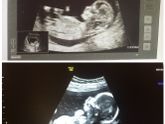

23 недели

Разница между первым и вторым скриннингами )) походу ей там очень комфортно)))